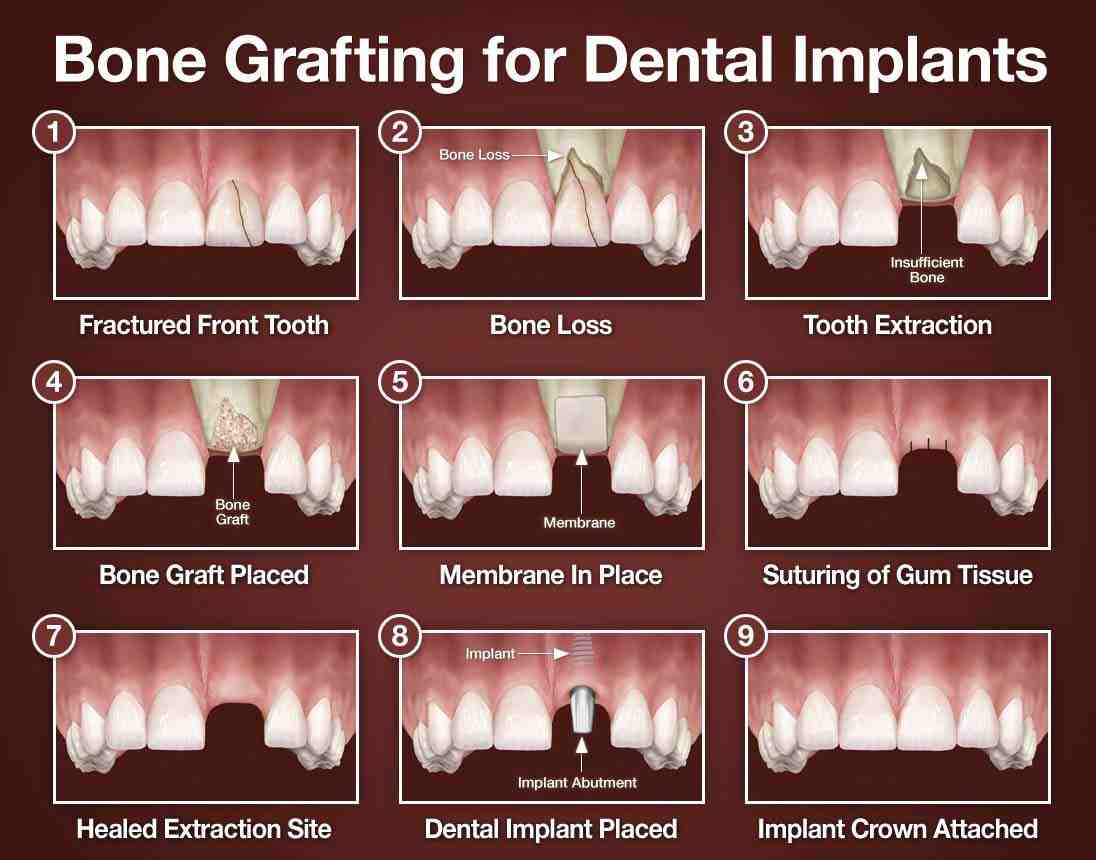

Implant Surgery Your dentist will place a titanium implant in your jawbone, just below the gums. This operation usually takes about 1-2 hours for each implant to be placed. On the same subject : How Much Are Denture Implants. Once this step is complete, most dentists will wait about 3 months before the final restoration of a tooth replacement.

All on 4 Dental Implant Cost You should be prepared to spend an average of around $25,000 per dental arch for this solution. This could be as little as $12,000 or as much as $50,000. The higher marks will come from additional factors that go into the procedure such as bone grafting to strengthen the jawbone.